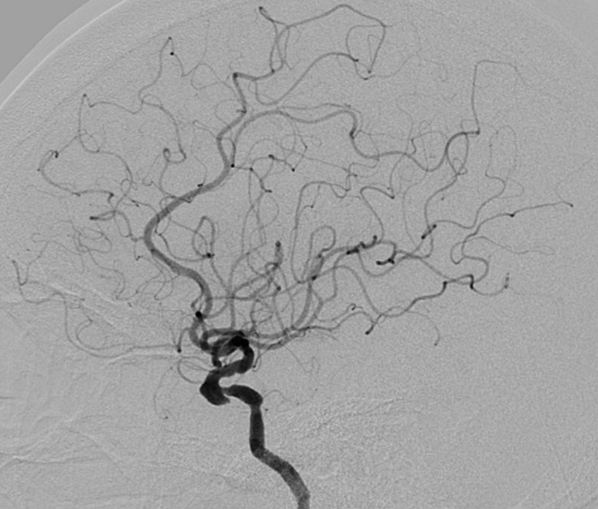

脑血管造影提示右侧颈内动脉颅内段多发动脉瘤(反主动脉弓)

脑血管造影提示右侧颈内动脉颅内段多发动脉瘤